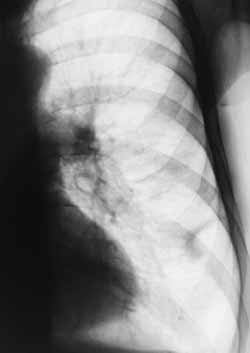

Лучевая диагностика периферического рака легкого.

Рис. 2. Рентгенограмма левого легкого. Периферический рак, развившийся на фоне рубца.

Новости лучевой диагностики 2001 1-2: 4-10